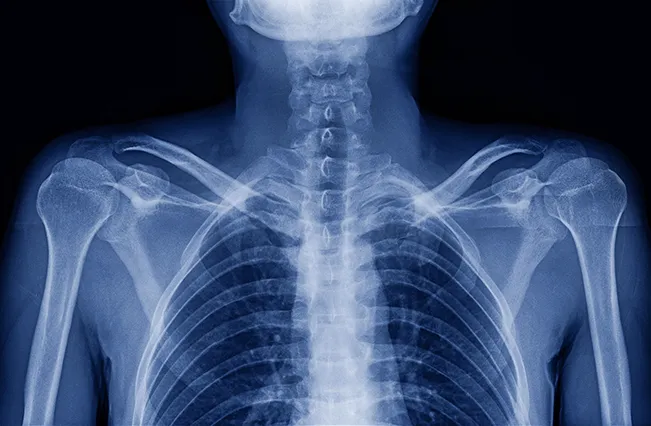

The most common source of true sciatica is a disc bulge or herniation at L4-L5 or L5-S1 pressing on a nerve root.

A shifted lumbar vertebra narrows the foramen where nerve roots exit the spine. This foraminal stenosis can produce identical symptoms to.

We do not guess which level is compressed. Structural imaging, neurological assessment, and orthopedic testing map the exact source of nerve irritation — whether it is disc herniation, stenosis, or a mechanical misalignment putting pressure where it should not be.